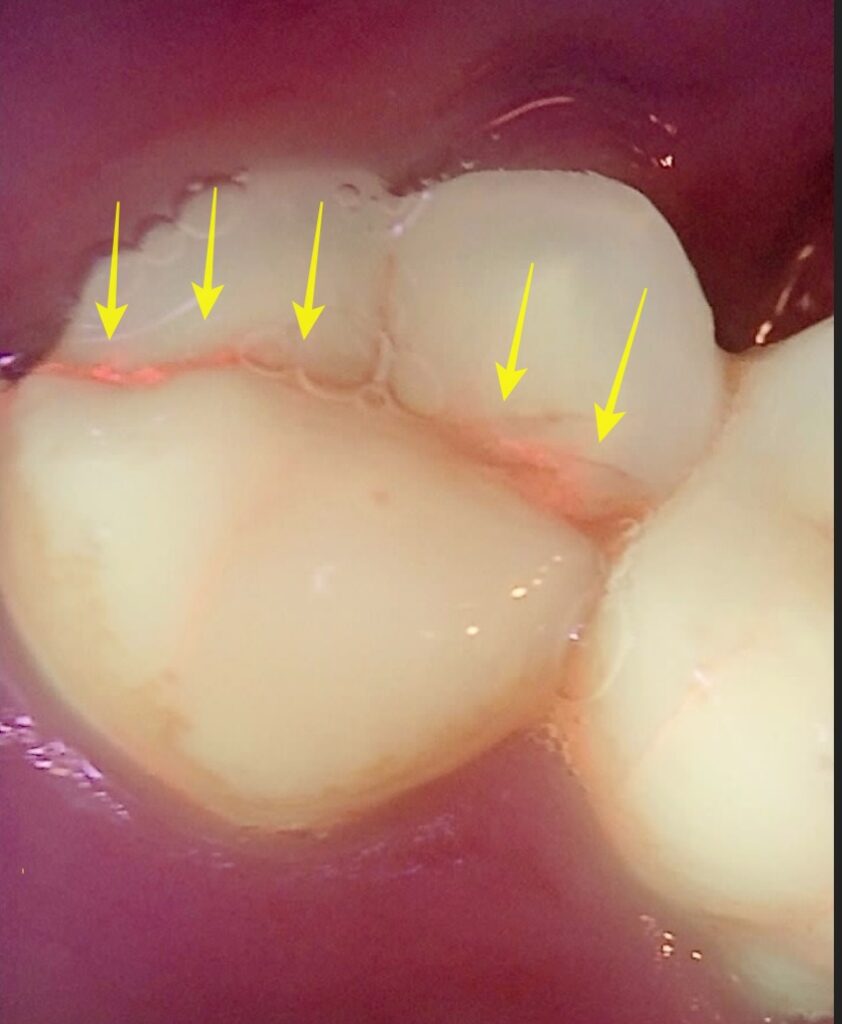

​한 환자분께서 씹을 때의 통증으로 타 치과에 내원하셨으나, “양치질을 너무 세게 하신 것 같아요. 살살하세요.” 하고 문제없다고 하셨다고 합니다. 상세히 봐주지 않은 것 같다는 의구심이 들었고 저희 치과에 소개를 받아서 내원하셨다고 하네요.

​해당 부위를 큐레이뷰로 촬영한 결과, 붉은 형광 반응이 관찰되었습니다.. 큐레이뷰는 세균의 활성도가 있는 부위를 빨간 형광의 물질로 보여줘서 충치나 치태, 치아균열 등을 진단하기 쉽게 해주는 장치입니다.

치아 균열증이 있었던 치아 – 다른 치과에서 제대로 진단하지 못하여 저희 치과에 내원하셨습니다.

치아 크랙

큐레이 촬영을 통해 크랙을 명확하게 확인할 수 있었고 신경치료를 통해 적절하게 치료 마무리 하였습니다.

환자분은 오랜 불편감에서 해방될 수 있었습니다.